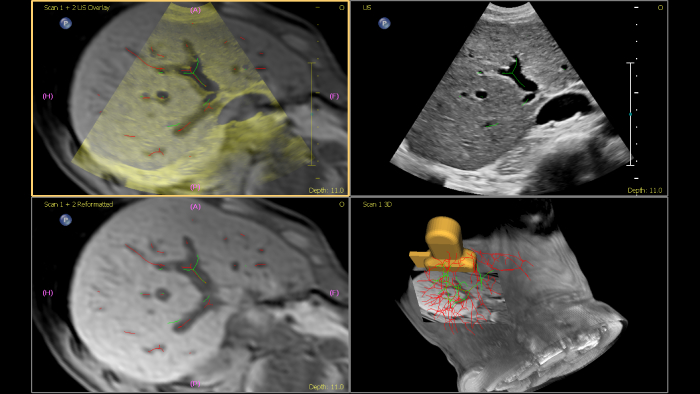

Philips ultrasound systems for interventional radiology support a range of sophisticated capabilities for interventional applications. Streamlined workflow allows clinicians to achieve fast and effective fusion of CT/MR/PET/CBCT with live ultrasound, while needle navigation aids in guiding biopsy and ablation of small and difficult-to-access lesions. Fusion and navigation can also be used in conjunction with Contrast-Enhanced Ultrasound (CEUS), giving clinicians access to even more powerful diagnostic tools with advanced visualization.

This semi-automated tool helps outline a 3D contour around a structure of interest, improving procedure guidance even in challenging cases where the lesion may not be visually obvious under ultrasound. The lesion can be rendered in 3D or 2D via a complementary modality and overlaid on the live ultrasound or CT, helping visualize the location in relation to surrounding critical structures.

Offering the industry’s only interventional workflow with CT-only needle navigation on an ultrasound system, image fusion and needle navigation unlocks flexibility and opens up new possibilities by making image fusion and the use of ultrasound imaging completely optional. Needle location in relation to CT is tracked and updated in real time for procedural visualization, allowing providers to tackle complex cases and anatomy, even where ultrasound imaging is not possible. Continuous patient tracking technology. Once the registration step is complete, the patient can move, change position, and the field generator can be moved in or out of the procedure space without losing anatomical landmarks or diminishing tracking accuracy.